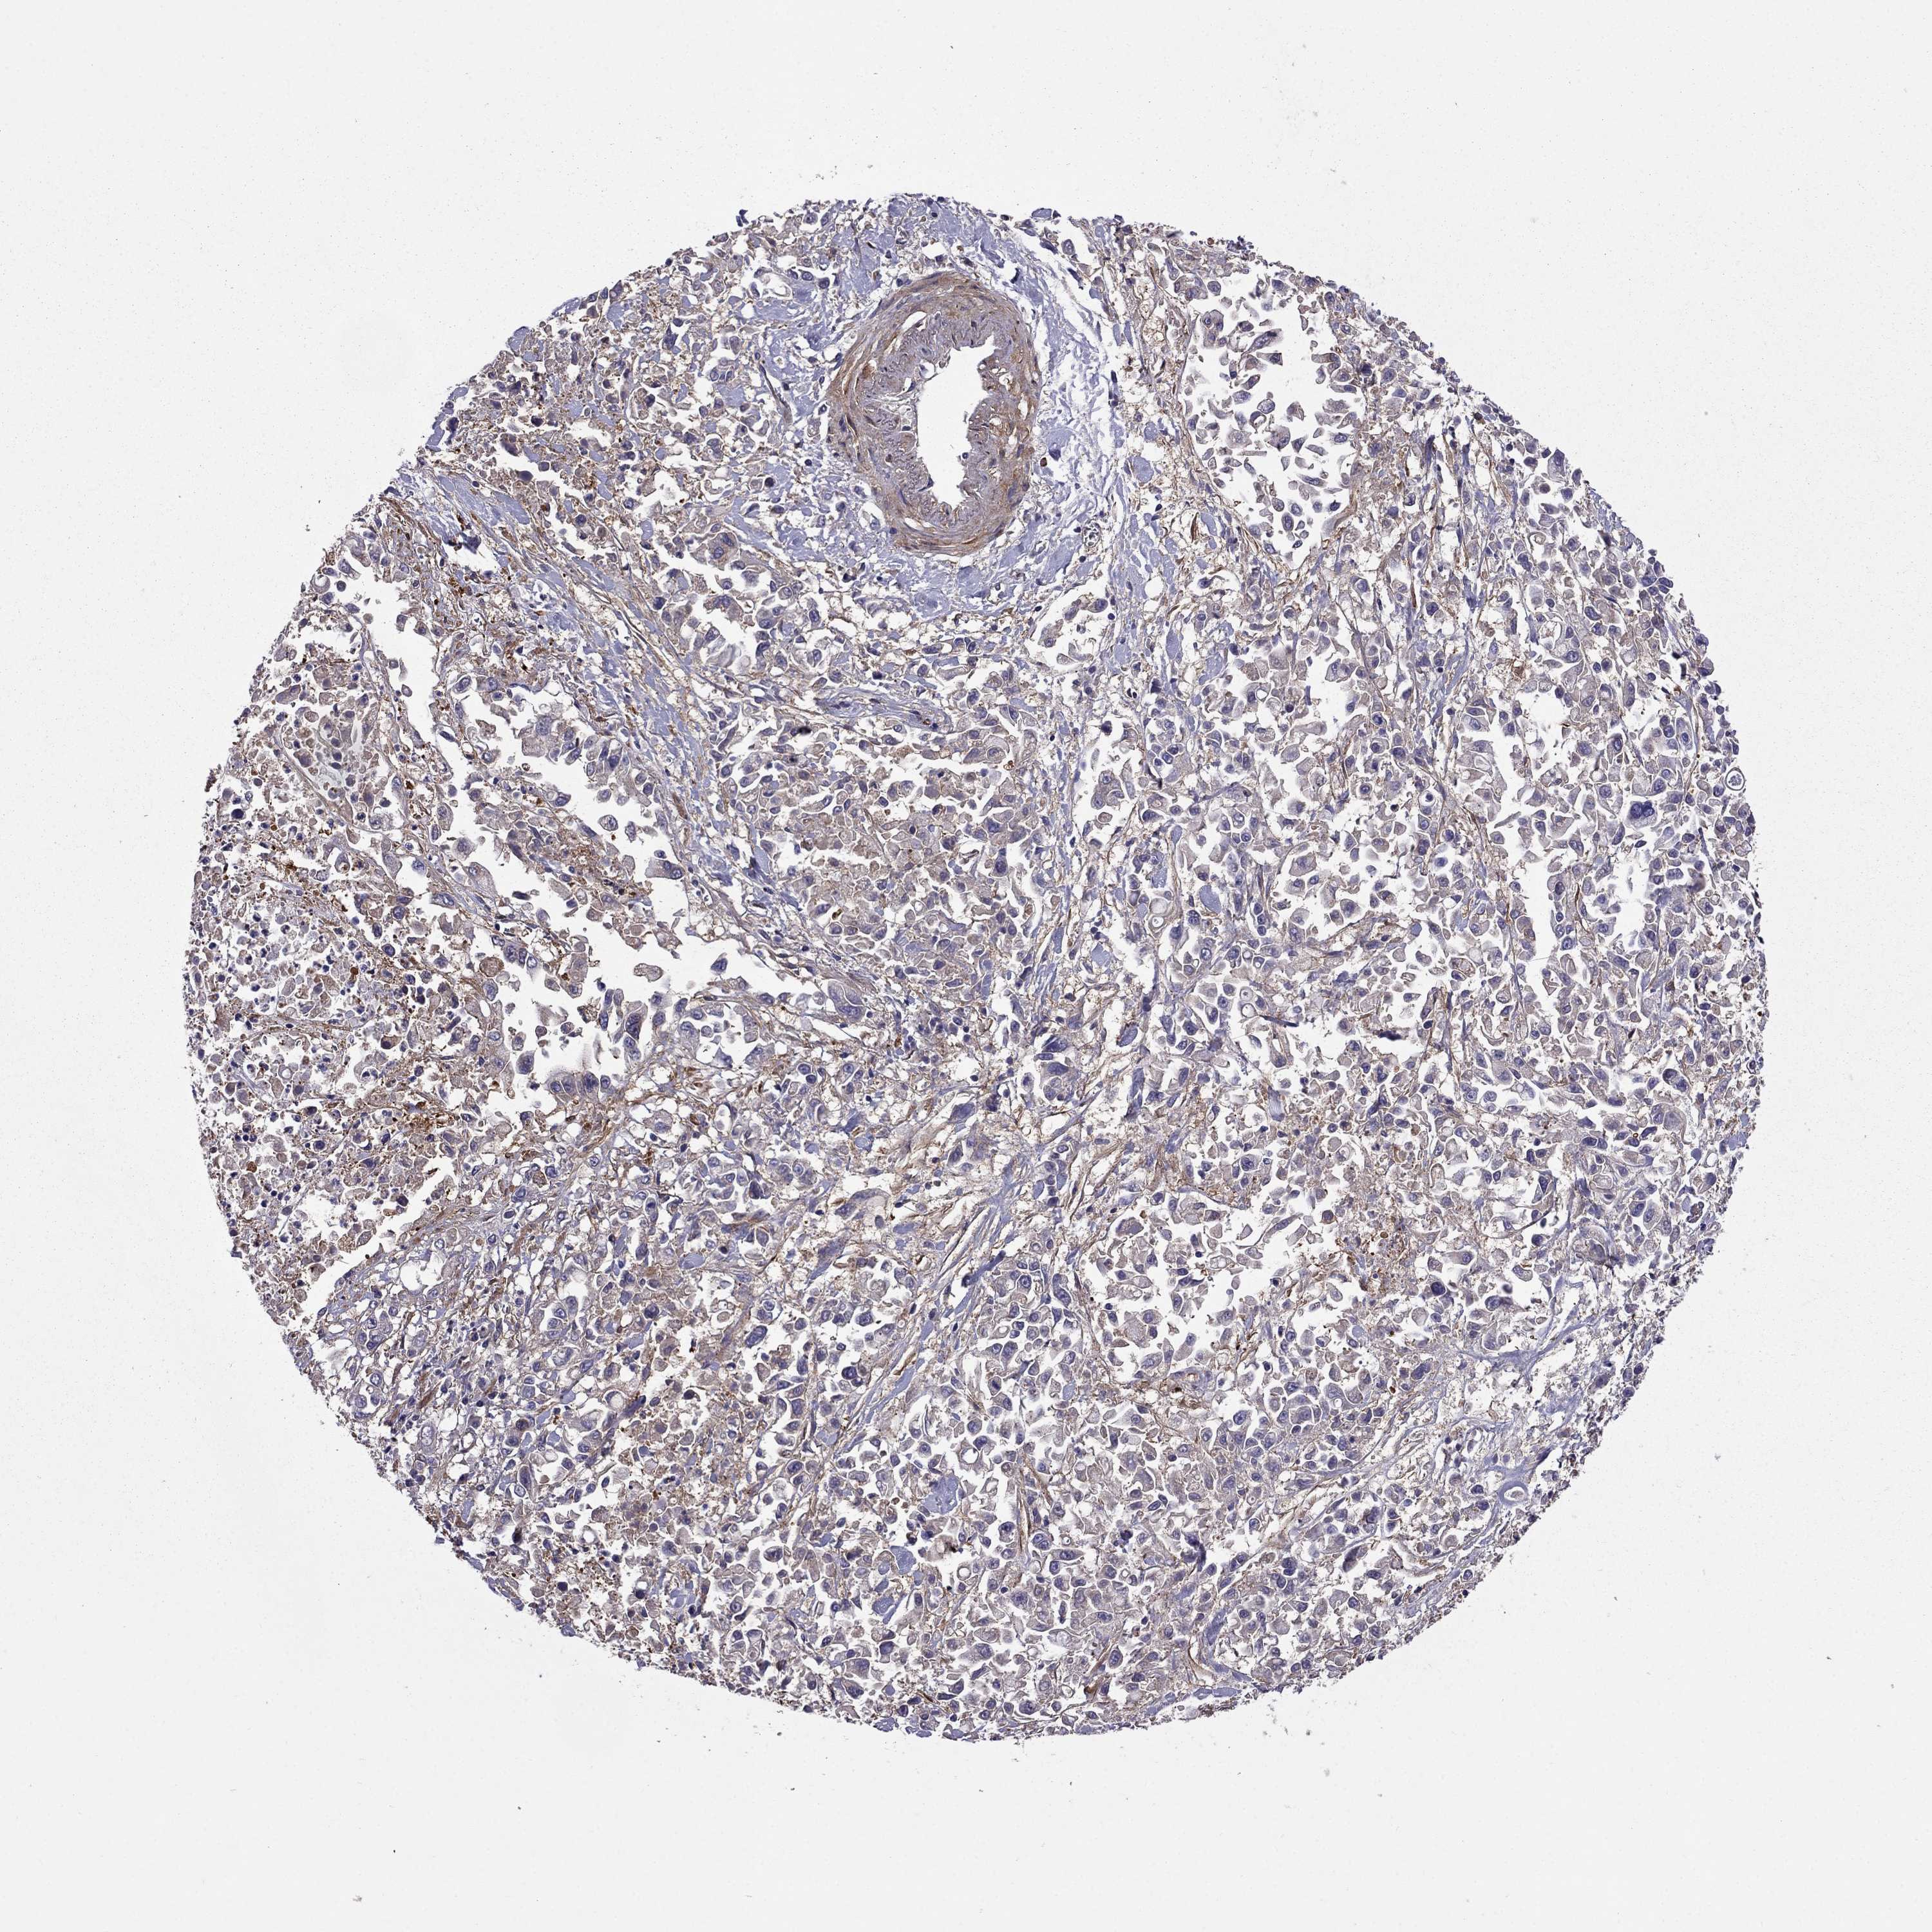

PANCREATIC CANCER - Protein expressioni

A mouse-over function shows sample information and annotation data. Click on an image to view it in a full screen mode. Samples can be filtered based on level of antibody staining by selecting one or several of the following categories: high, medium, low and not detected. The assay and annotation is described here.

Note that samples used for immunohistochemistry by the Human Protein Atlas do not correspond to samples in the TCGA dataset.

Antibody stainingi

Antibody staining in the annotated cell types in the current human tissue is reported as not detected, low, medium, or high, based on conventional immunohistochemistry profiling in selected tissues. This score is based on the combination of the staining intensity and fraction of stained cells.

Each image is clickable and will lead to virtual microscopy that enables deeper exploration of all samples and also displays staining intensity scores, fraction scores and subcellular localization as well as patient and tissue information for each sample.

Antibody HPA059297

Antibody HPA069003

Antibody CAB003434